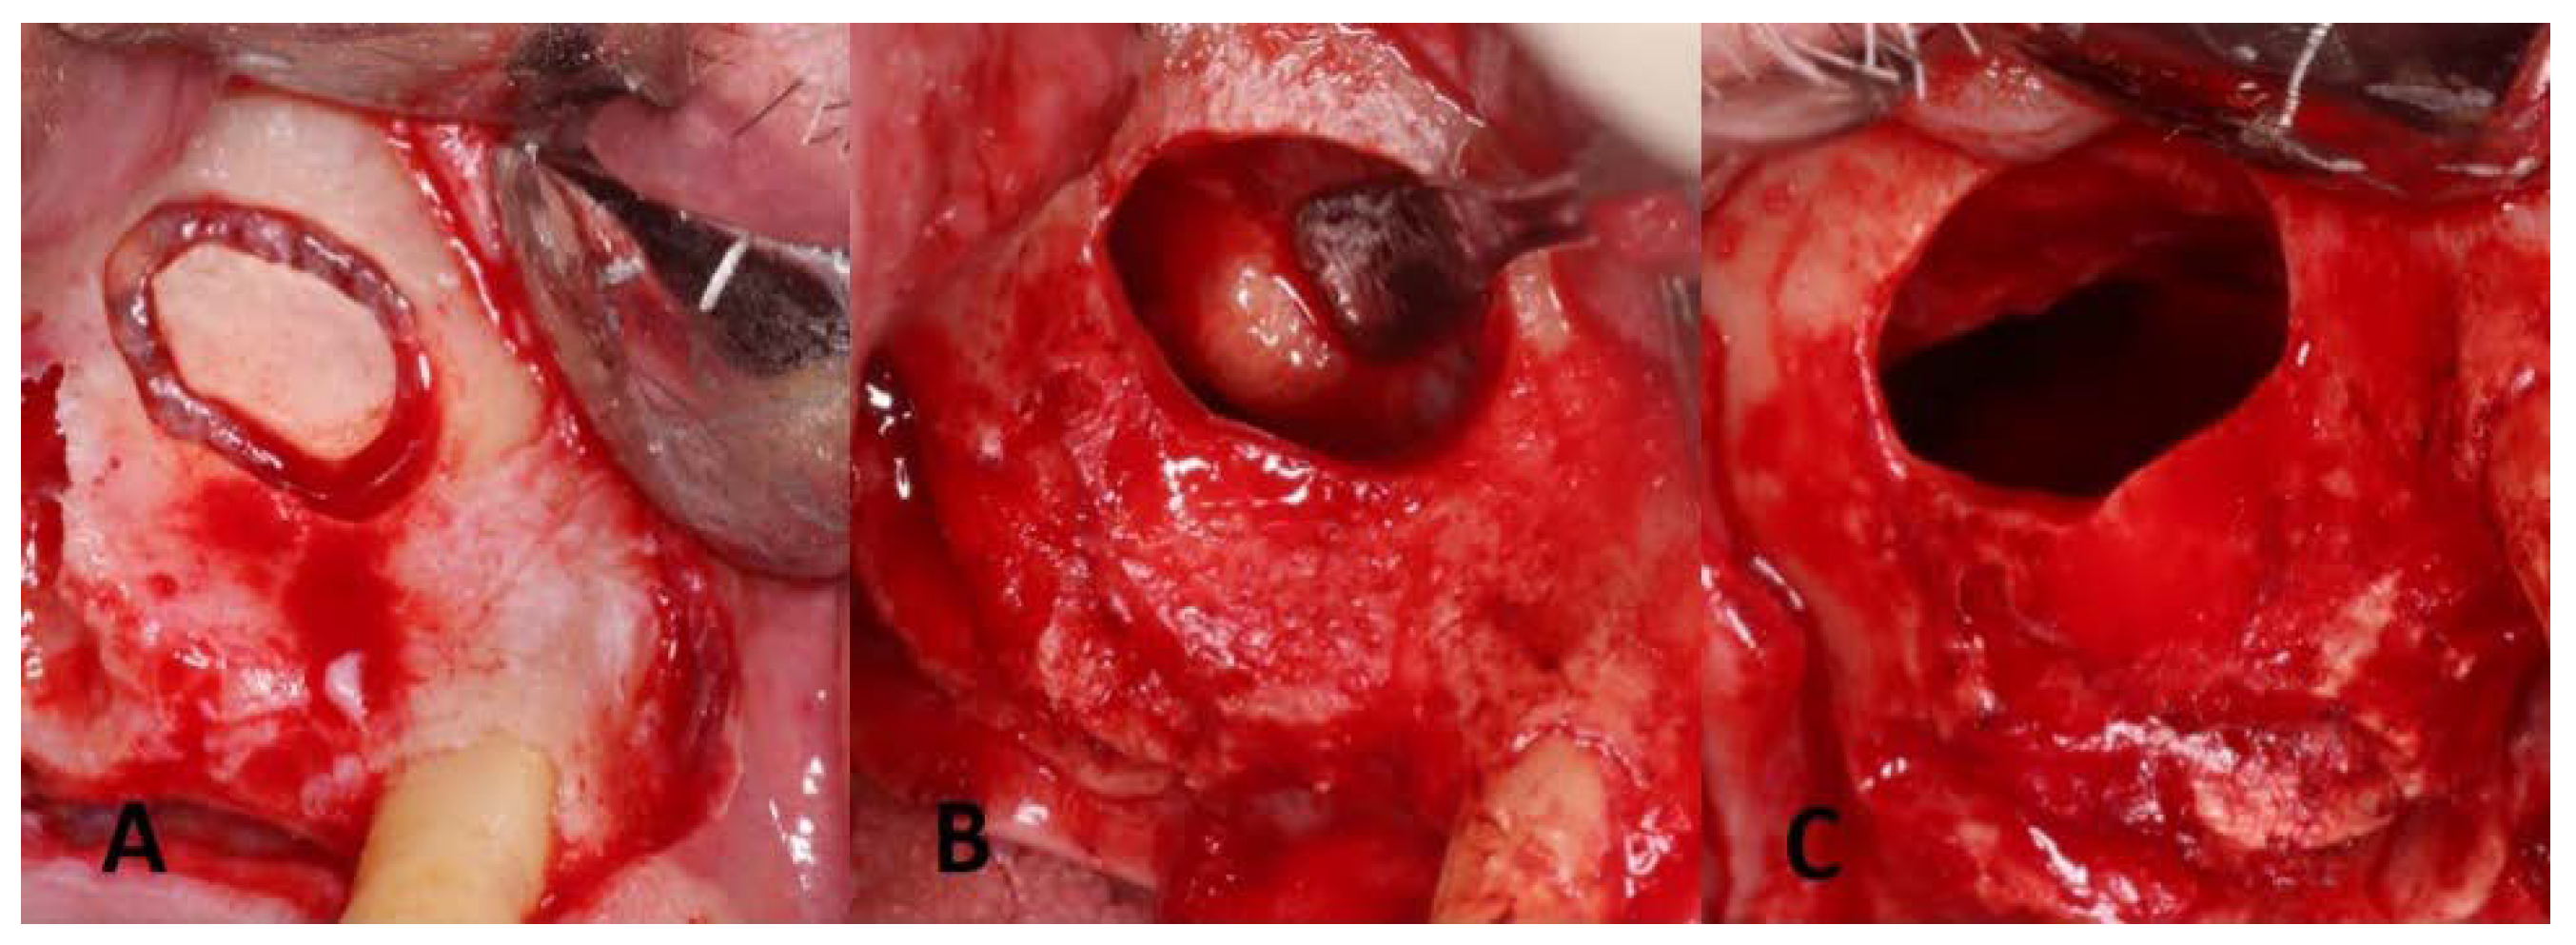

3. Surgical Procedures